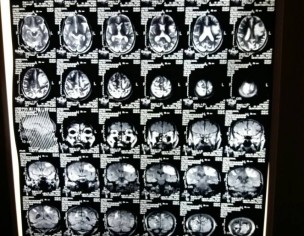

He as been gone through five brain/mental attacks, and he gets weaker after every attack. his left hand and tongue is not working properly, and he cannot walk without our support. His MIR result shows that he has a small brain tumour/brain TB infection, according to Jailani Hospital - Quetta, Pak. He is taking medicine, but no health improvement seen so far.

Did you see and examine the above MIR pictures that I have attached with my post. If yes, how will you explain it.

I mean do you agree with his doctor who says that he has brain TB/tumour?

Have seen the MRI reports that's why I commented about SOL but it s very difficult to reach on exact diagnosis only on the basis of further history like the duration of symptoms, any fever ,wt loss and also examination .he will definitely need surgery to release the pressure on brain ......